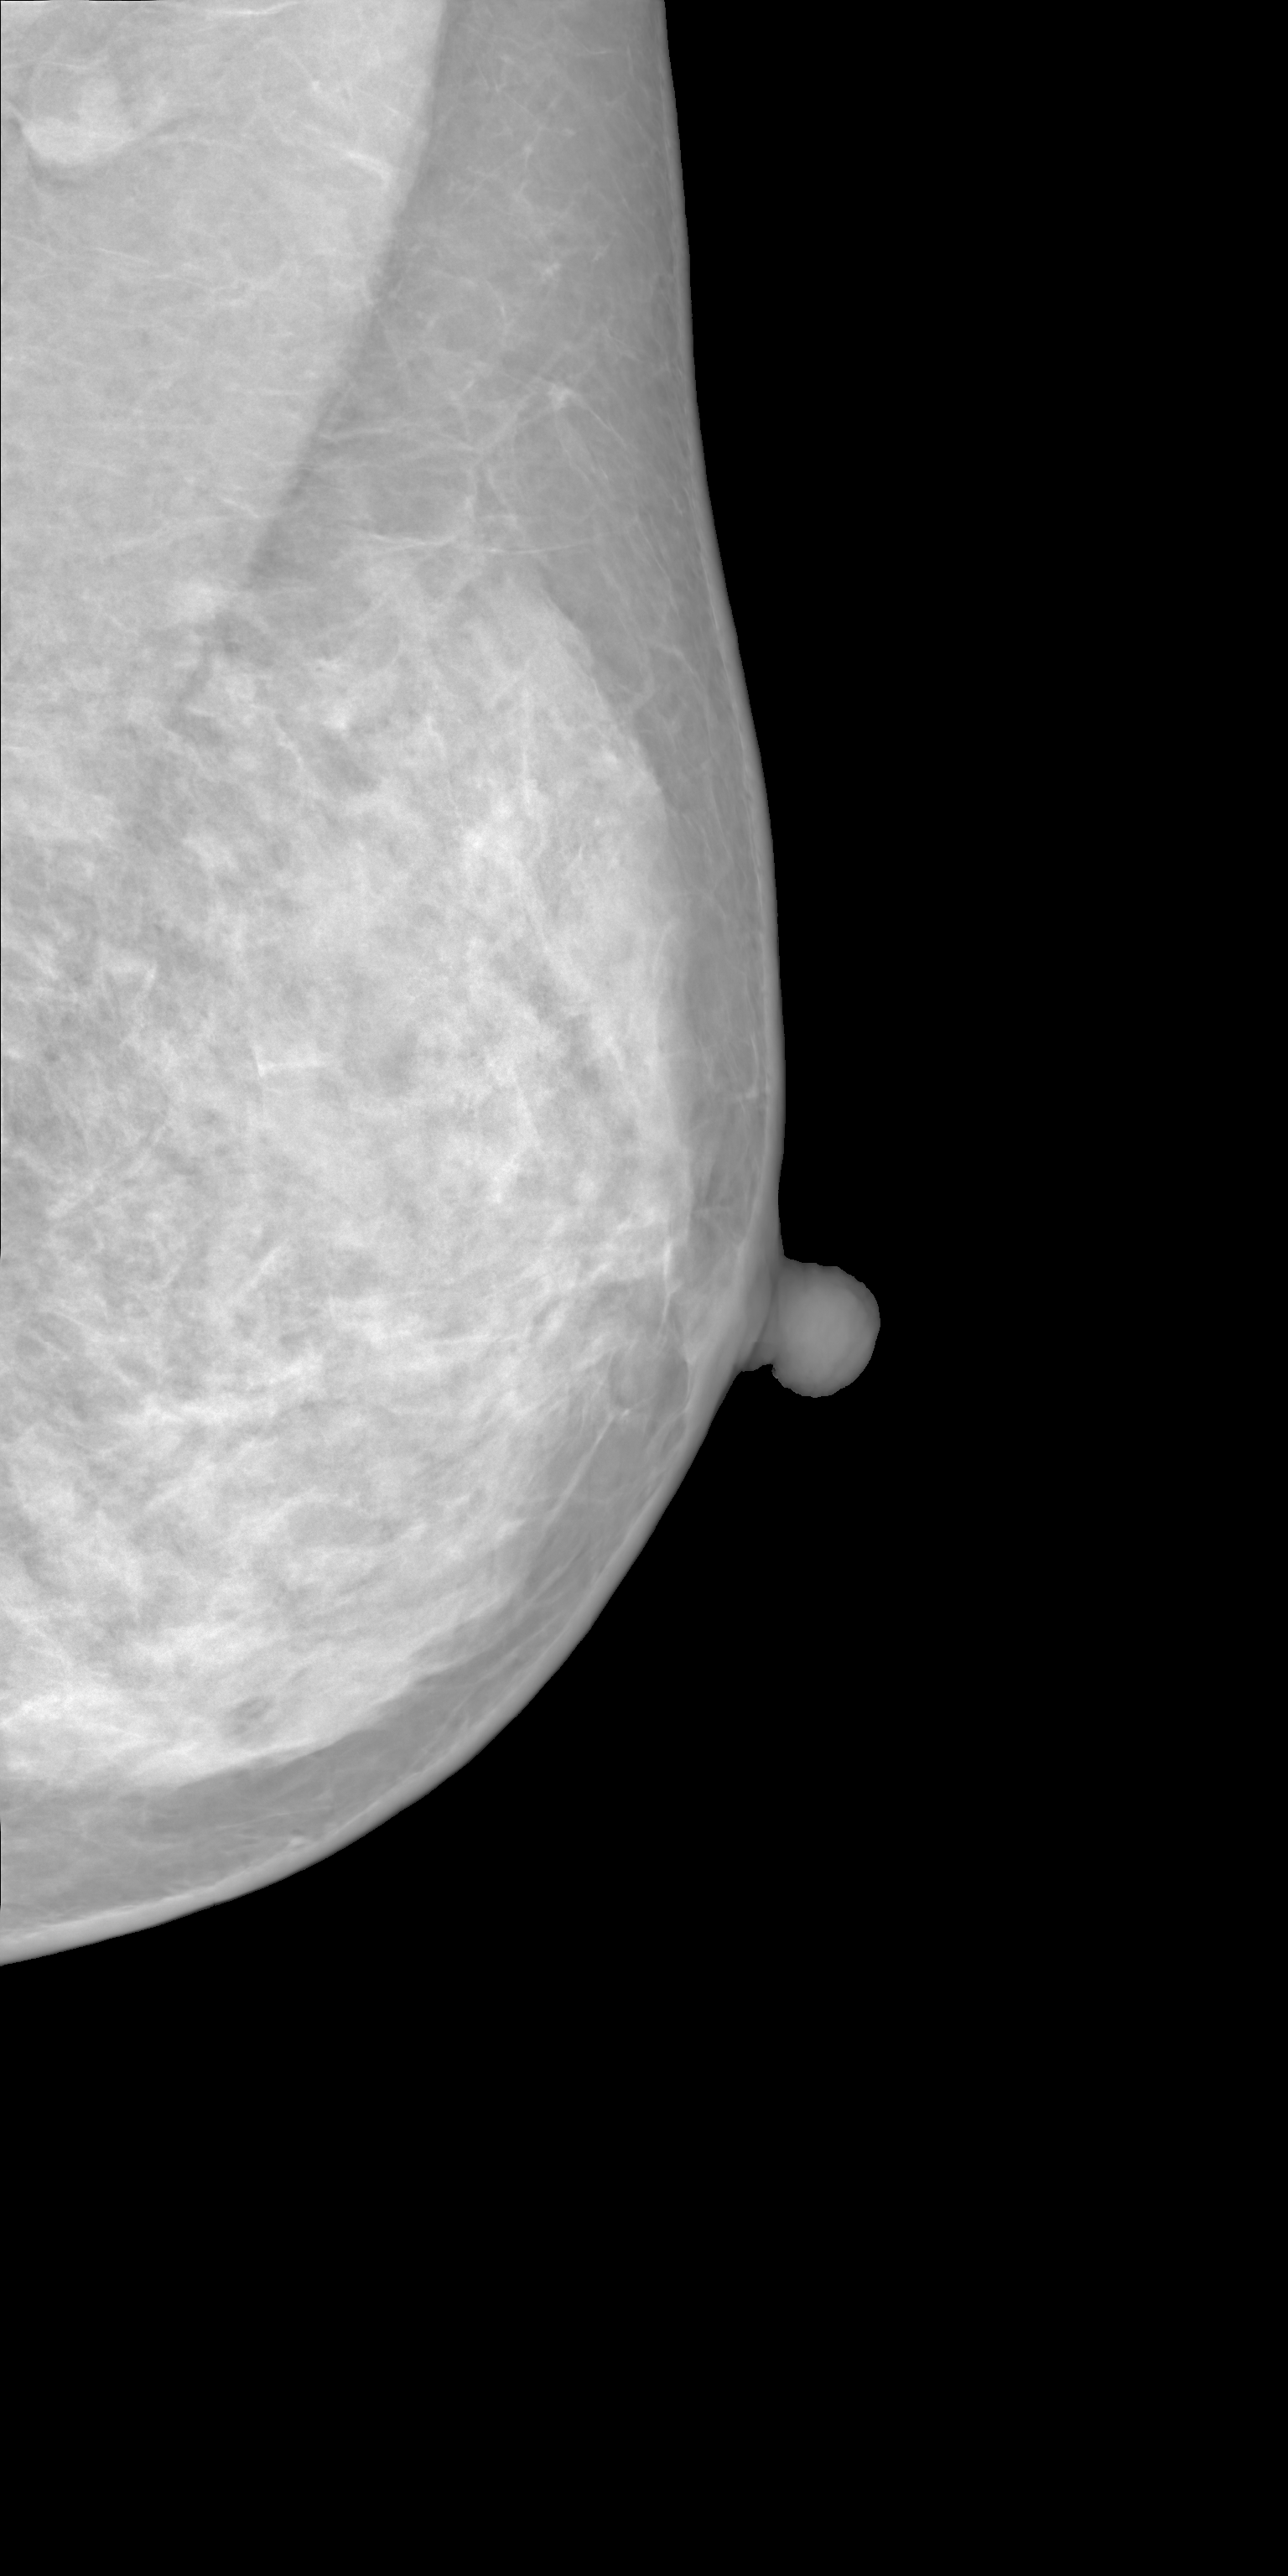

Fig. 3(d) illustrates what MAMBO can achieve in terms of whole mammogram generation. When using global and local context data extracted from an original image, the denoised image (Fig. 3(b)) is difficult to distinguish from the original (shown in Fig. 3(a)). When providing only the original global context and generating local context and target patches from noise, we still observe good results, as we show in Fig. 3(d).

The mammograms generated using MAMBO (all three models connected in a pipeline) are shown on Fig. 13 and Fig. 14. The model is designed to generate full-square images to accommodate varying breast proportions. However, the provided examples are cropped to focus solely on the breast region.

17 Examples of Lesions on Images Generated by MAMBO Annotated by Experts